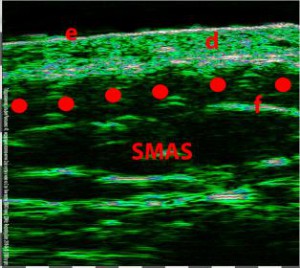

-Έγχυση Πληρωτικών Υλικών (Fillers)

-Lifting με νήματα

-Μέθοδοι θεραπείας υψηλής ενέργειας

(λέιζερ, RF-Ραδιοσυχνότητα, HIFU-Υψηλής Έντασης Εστιασμένος Υπέρηχος, κ.λπ.)